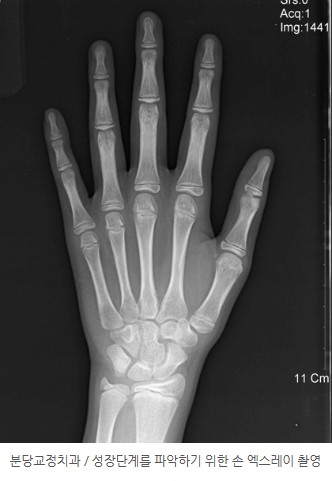

9. 성장 단계 평가의 중요성 – 손 엑스레이(Hand–Wrist Radiograph)

성장기 교정의 핵심은 **“언제 시작하느냐”**입니다.

아이마다 성장 속도와 급성장 시기가 다르기 때문에, 단순히 나이 만으로는 판단하기 어렵습니다.

이 증례에서도 치료 시기를 정확히 잡기 위해

**손 엑스레이(hand–wrist radiograph)**를 촬영하여 성장 단계를 평가했습니다.

손 엑스레이를 통해,

를 객관적으로 판단할 수 있습니다.

같은 2급 부정교합이라도,

치료 전략과 결과가 크게 달라질 수 있습니다.

따라서 성장 단계에 맞춘 1·2차 교정 계획 수립이 매우 중요합니다.